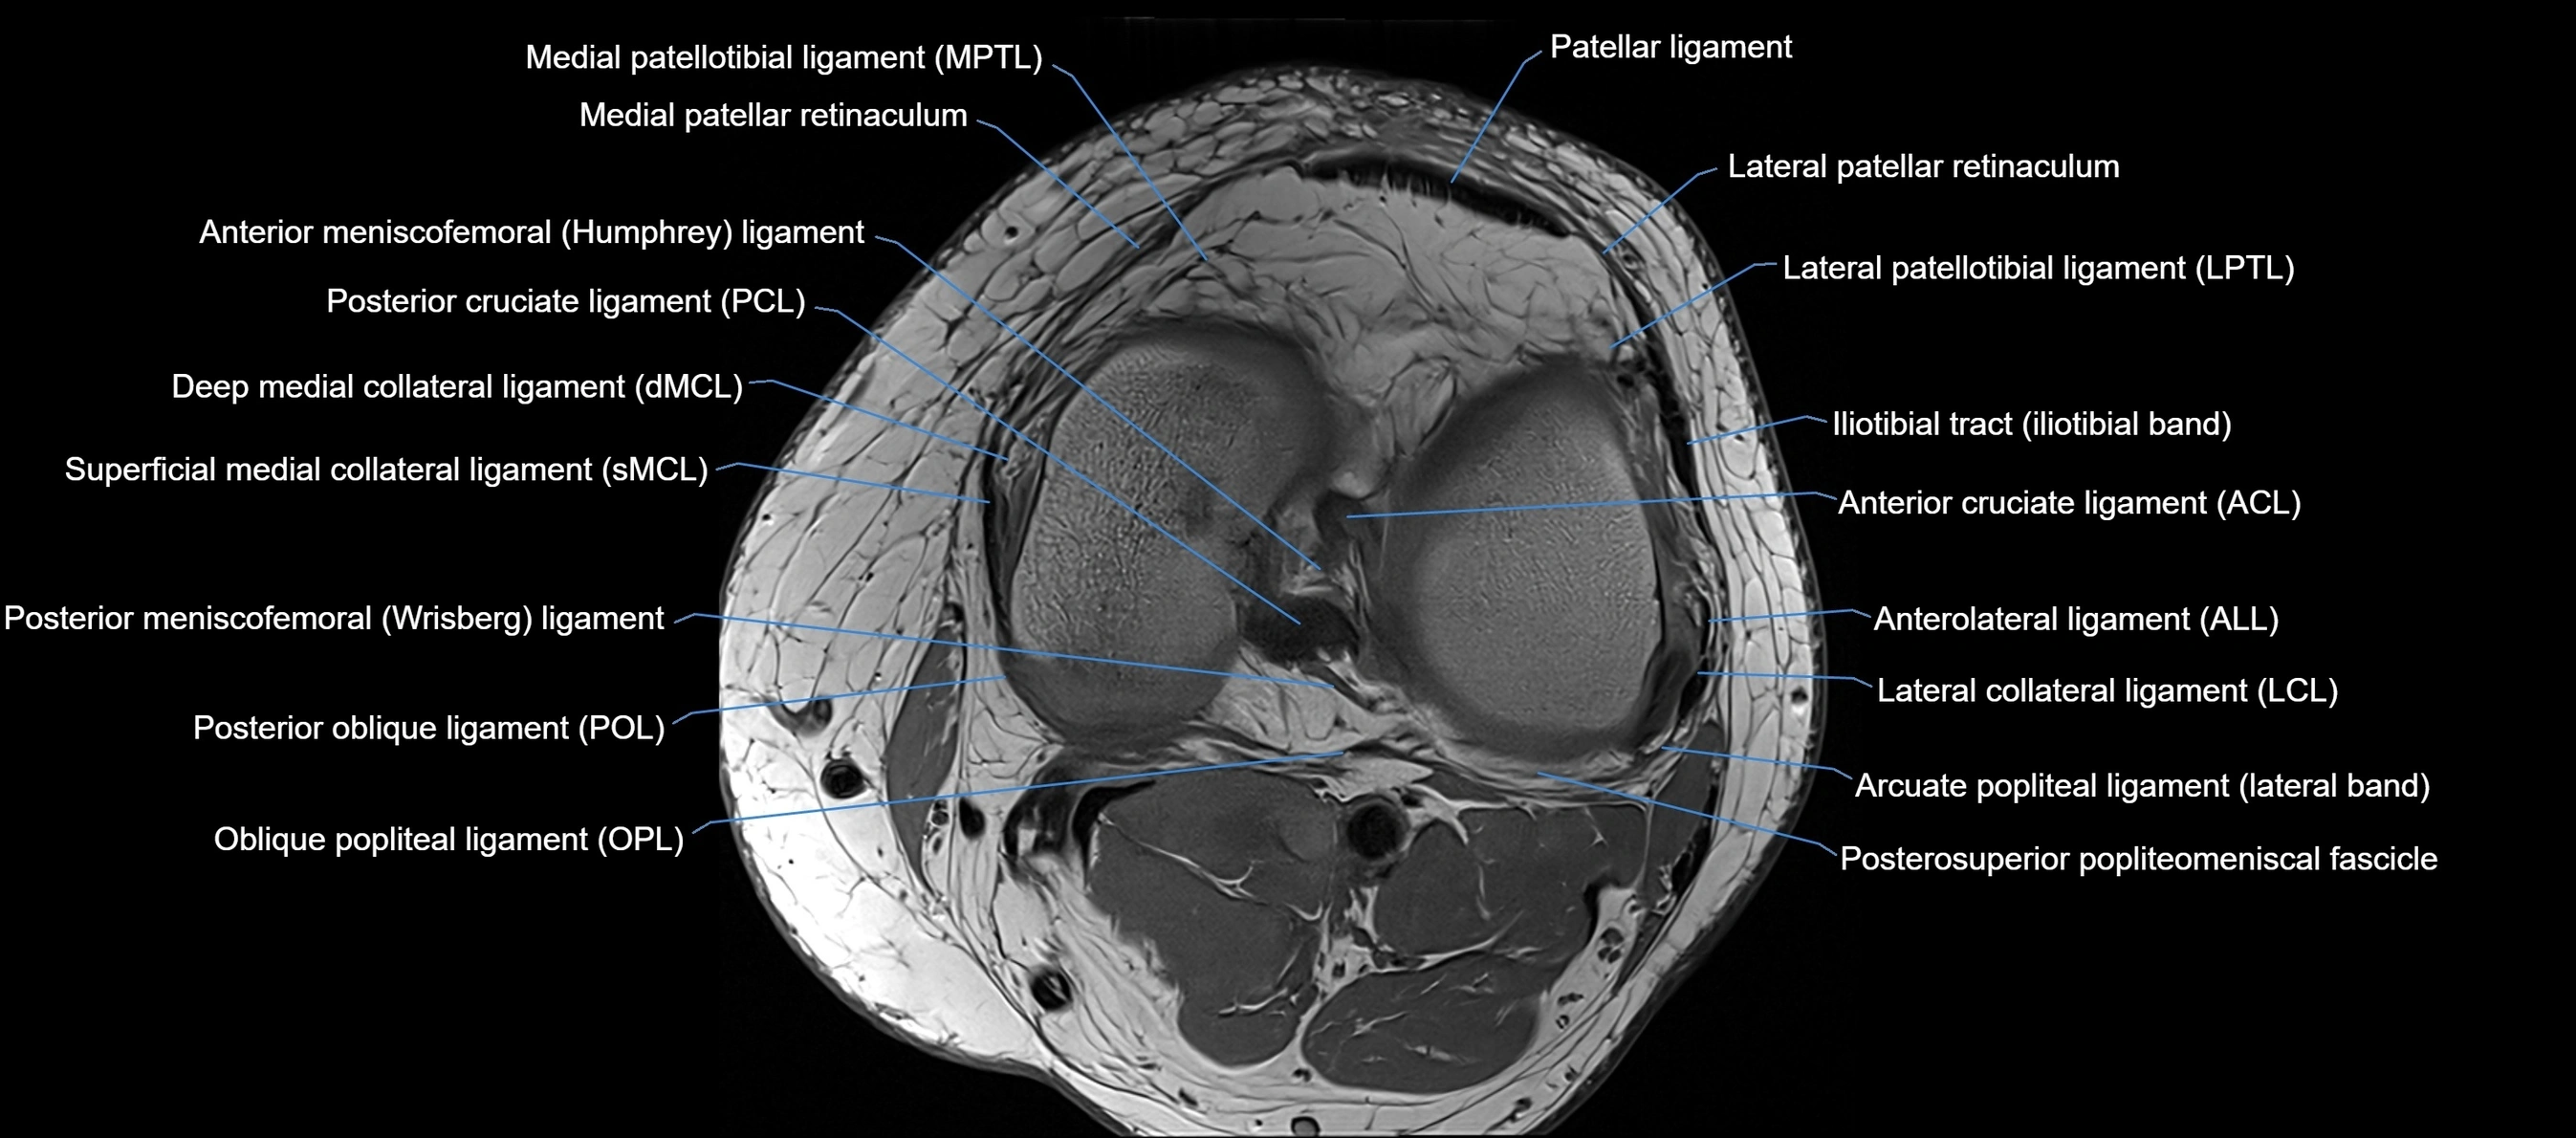

MRI images

image

MRI Appearance

Proton Density Fat-Saturated (PD FS):

• Normal ACL: dark, low-signal band

• Tears: bright intraligamentous hyperintensity, discontinuity, or abnormal course

T1 Fat-Sat Post-Contrast:

• Normal ACL shows little or no enhancement

• Inflamed, vascularized, or reconstructed grafts may show enhancement

• Post-surgical scarring or synovitis may show enhancing tissue around graft